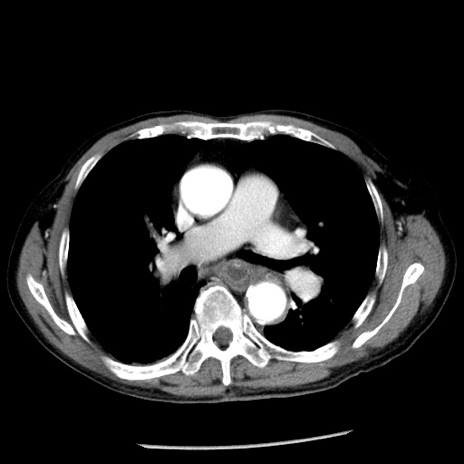

症例26(横断像)

【症例】80歳代男性

【主訴】嘔吐

【現病歴】昨晩2回嘔吐あり、今朝になっても嘔吐あり。来院。

【既往歴】胃潰瘍

【身体所見】意識清明、BT 37.6℃、BP 166/95mmHg、HR 100bpm、SpO2 97%、腹部:平坦・軟、腸蠕動音聴取良好、圧痛なし。

【データ】WBC 21900、CRP 1.46